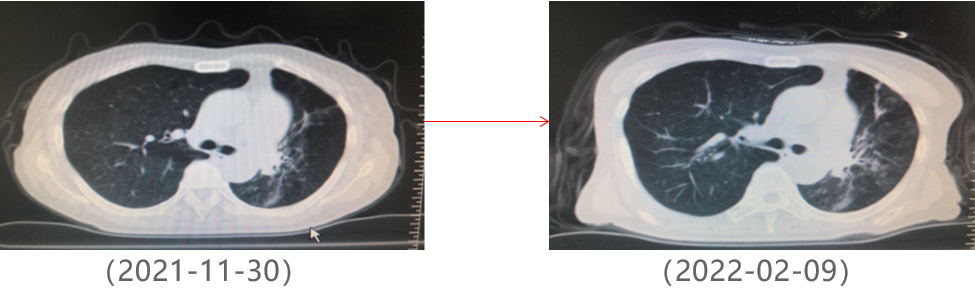

为提升肺癌前线免疫联合抗血管治疗的诊疗观念,学习与追踪肺癌领域诊疗最前沿知识,充分交流免疫/抗血管用药不良反应管理临床经验,【An例说】肺癌病例项目,征集大量临床高质量免疫联合抗血管治疗肺癌病例,并邀请全国各区域中青年及高职称医生与顶级TOP KOL互动发声!通过理念结合实践,研究结合病例,线上联动,共同促进学术由KOL/ROL向中青年医生下沉,为提升我国肺癌诊疗整体水平势在必行。免疫治疗的出现,特别是以PD-1/PD-L1为代表的免疫检查点治疗的出现,对于转移性的晚期肺癌患者而言,给患者增加了更多治疗的选择,同时,多项临床研究表明免疫治疗显著延长了患者的生存期及生活质量。为此,河北北方学院附属第一医院为您带来一例“双安疗法”用于二线治疗小细胞肺癌病例的治疗分享。 案例详情 基本情况 患者,霍xx,女,60岁。 初治时间:2020-10-16 既往史:COPD 4年,间断口服茶碱治疗,否认其他慢性病史及传染病史。否认过敏史。 个人史:无特殊 家族史:无特殊 ADL评分:90分;Khorana评分1分 入院初步检查结果 体格检查: COPD 4年,间断口服茶碱治疗,否认其他慢性病史及传染病史。否认过敏史。 个人史、婚育史、家族史无特殊。 辅助检查 血常规、肝肾功、凝血功能无明显异常。 肿瘤标志物(特异性+异常指标)。 肿瘤标志物变化趋势 NSE(神经元特异性烯醇化酶)变化趋势: NSE变化趋势 基线情况: 2020-10-16,患者无明显诱因出现咳嗽、咳痰,偶有痰中带血,伴胸闷气短4个月于我院就诊:查胸部CT:胸廓左侧塌陷,左肺上叶尖后段及下叶支气管截断,左肺下叶见软组织密度团块。右肺中叶容积小。左主支气管内见高密度影,纵隔多发肿大的淋巴结,胸膜厚,左侧少量胸膜腔积液。 浅表淋巴超声、全身骨扫描等检查提示肺外脏器未见异常。 肺部CT提示左肺占位伴阻塞性肺炎、纵隔淋巴结肿大,左侧胸腔积液。 患者遂就诊于解放军81集团军医院行支气管镜检查提示小细胞肺癌。 影像学检查 诊断结果 1.左肺小细胞肺癌(广泛期)伴胸膜转移、伴纵隔淋巴结转移 2.阻塞性肺炎 3.慢性阻塞性肺疾病 诊疗依据 (CSCO)小细胞肺癌诊疗指南2020 05治疗经过 第一阶段治疗: 胸部CT对比:较前片(2020-10-16)对比:左肺上叶复张且高密度影明显吸收;左肺占位及纵隔淋巴变化不明显,左侧胸腔积液基本吸收。 胸部CT检查对比 胸部CT对比:较前片(2020-11-26)对比:左肺占位变化不明显;纵隔部分淋巴结增大。 胸部CT检查对比 胸部CT对比:较前片(2020-12-30)对比,左肺占位明显增大,隔巴结增大,左侧胸腔新发积液,左肺上叶膨胀不全,左肺上叶新发片状高密度影。 胸部CT检查对比 胸部CT对比:较前片(2021-03-02),左肺占位性病变较前增大,纵膈肿木淋巴结较前增大。 胸部CT检查对比 胸部CT对比:较前片(2021-04-04)左肺中心型肺Ca伴左肺不张,较前增大。右肺中叶不张。纵隔多发肿大融合淋巴结,部分包绕上腔静脉,较前增大。心包少量积液、主肺动脉干增粗。左侧胸腔积液(±)。 胸部CT检查对比 头颅CT对比:2021-06-21头颅CT:考虑左枕叶、右颞叶转移瘤。尾状叶头密度增高。 头颅CT检查对比 腹部CT:较前片(2021-04-04)左肾上腺增粗,考虑转移瘤? 腹部CT检查对比 第二阶段治疗:免疫+安罗替尼。ADL评分:70分;Khorana评分3分。 胸部CT对比:对比前片(2021-06-21),左肺占位减小,纵隔部分淋巴结减小,胸腔积液吸收。 胸部CT检查对比 头颅CT对比:对比前片(2021-06-21):颅内占位变化不著。 头颅CT检查对比 胸部CT对比:对比前片(2021-07-27):左肺占位减小,纵隔部分淋巴结减小;左肺上叶片状高密度影略显吸收。 胸部CT检查对比 胸部CT对比:对比前片(2021-8-23):左肺占位及纵隔淋巴结有所减小。 胸部CT检查对比 胸部CT对比:对比前片(2021-10-29):左肺占位及纵隔淋巴结变化不著。 胸部CT检查对比 头颅CT对比:较前片(2021-07-01)对比:左枕叶、右颞叶占位明显减小。 头颅CT检查对比 胸部CT对比:对比前片(2021-11-30):左肺占位及纵隔淋巴结变化不著,腹部较前变化不著。 胸部CT检查对比 目前情况:患者神清,精神尚可,无咳嗽咳痰,偶有喘憋气短,饮食睡眠尚可,二便正常。 面部及双手皮疹样改变。 目前诊断: 1. 左肺小细胞肺癌(广泛期)伴胸膜转移、伴纵隔淋巴结转移、伴脑转移、伴肾上腺转移 2. 慢性阻塞性肺疾病 3. 下肢静脉血栓形成 4. 低钠血症 ADL评分:80分;Khorana评分2分 06病程回顾 专家点评 该病例,女性,无吸烟史,既往自2014年开始反复因咳嗽、咳痰、咯血于我院门诊或住院治疗,诊断为右中叶、双下肺基底段支气管扩张伴感染。2020年10月再次因咳嗽、咳痰、咯血行肺CT检查,检查结果示:支气管扩张、左下肺占位。后经支气管镜检查左下肺癌,病理为小细胞癌。结合肺CT:纵隔淋巴结肿大,左侧胸腔积液;临床诊断为:原发性支气管肺癌(左下广泛期小细胞肺癌)。PS评分1分,依据2020年CSCO小细胞肺癌指南Ⅰ级推荐选择化疗+免疫治疗,化疗方案:CE/EP,IC/IP,免疫治疗:atezolizumab。本病例中,患者因经济条件所限,未使用atezolizumab,化疗采用CE\EP\ZP一线及二线LE(共计7疗程),肺部病灶增大,左肺完全不张,脑转移,肾上腺转移,PS评分3分。再次依据CSCO指南,行颅脑放疗,采用PD-1(卡瑞丽珠单抗)+EP+安罗替尼(口服小分子多靶点抗血管生成药物)2个疗程后,肺部病灶明显缩小,颅内病灶消失,评效为PR;后因卡瑞丽珠单抗副作用:反应性皮肤毛细血管增生症(RCCEP)及手部皮肤皲裂,改换为派安普利单抗+EP+安罗替尼治疗,直至目前。左肺完全复张,病情明显改善,PS评分降至2分。 该患者全程治疗过程分析,单纯化疗疗效不显著,PD-1联合抗血管生成靶向药物后,使得患者病情控制,生存带来了希望。“双安”治疗方案副作用小,对PS评分高的患者也适用。派安普利单抗是唯一采用IgG1亚型且经FC段改造的新型PD-1单抗,副作用较国产其他IgG4亚型 PD-I更小;安罗替尼为口服小分子多靶点络氨酸酶抑制剂,靶点更加全面,疗效更优。采用“双安”治疗广泛期小细胞肺癌,本例虽为个例,但为临床医生提供了可践行的治疗方向,也期待着更多临床研究数据的公布,为小细胞肺癌的治疗提供强有力的治疗依据。 病例分享 王布 教授 河北北方学院附属第一医院呼吸科副主任医师,医学硕士 河北省中西医结合睡眠专业会委员 张家口市抗癌协会肺癌专业委员会委员 世界中医药学会联合会整合肿瘤专业委员会委员 在《Translational Cancer Research》、《Journal of biological regulators &homeostaticagents》、《中国临床药理学》、《中华结核与呼吸杂志》等杂志上发表学术论文10余篇,其中《川芎嗪联合顺铂影响Lewis肺癌小鼠移植瘤生长及微血管生成的研究》论文在2015年中国药学大会暨第十五届中国药师周上报告交流 荣获河北省科技进步三等奖1项,河北省医学会科技奖一等奖1项 目前以第一主研人主持河北省科技厅课题1项,市厅级课题2项 以第二主研人主持张家口市财政厅支持课题1项;河北省政府资助专科能力建设和专科带头人培养课题1项 获“河北省抗击新冠肺炎先进个人”、“河北省优秀共产党员”、“河北省冀青之星”、张家口市“最美科技工作者”,“张家口市抗击新冠肺炎先进个人”、“张家口市优秀共产党员”等荣誉称号。 专家点评 支学军 教授 河北北方附属第一医院主任医师 教授,河北北方学院硕士研究生导师 任河北省医学会内科学分会委员 张家口市医学会呼吸分会常务委员兼秘书 张家口市抗癌协会理事会理事 张家口市抗癌协会肿瘤临床化疗专业委员会常务委员 张家口市抗癌协会抗癌药物专业委员会常务委员等职务 从事呼吸科工作30余年,擅长肺部感染性疾病、肺癌、肺结核等疾病的诊治。